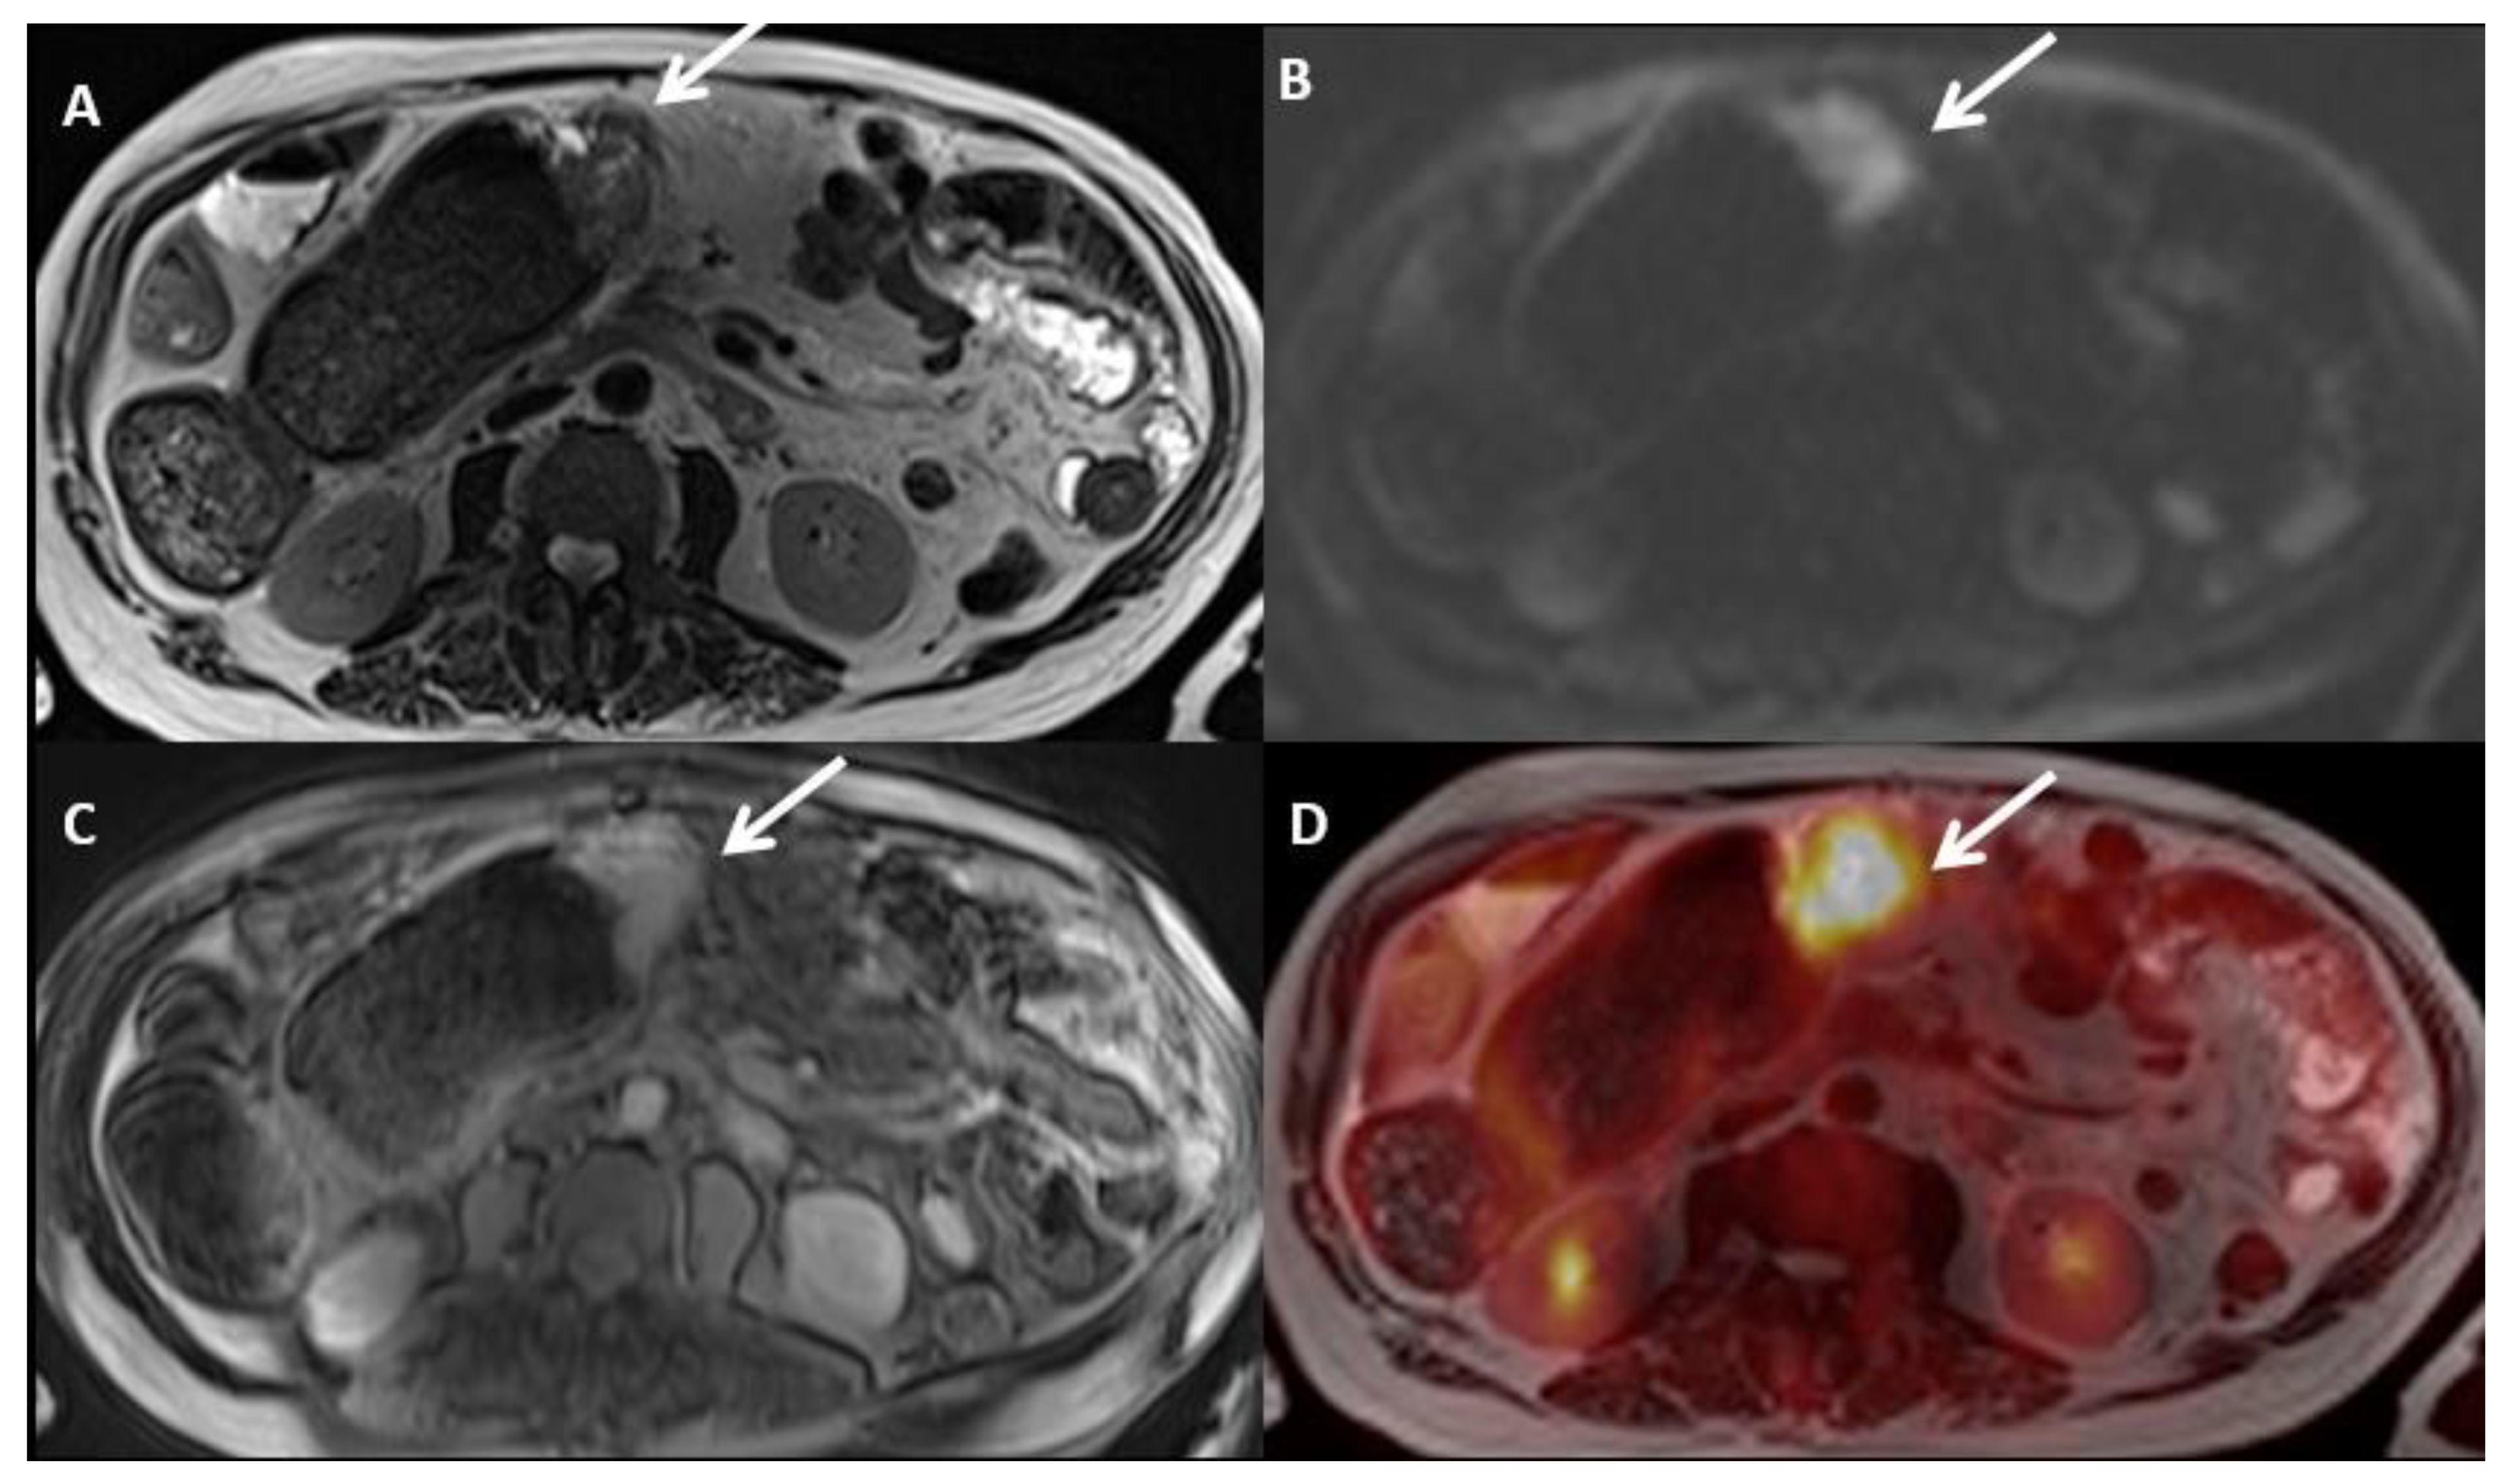

- Qin, C.; Shao, F.; Gai, Y.; Liu, Q.; Ruan, W.; Liu, F.; Hu, F.; Lan, X. 68Ga-DOTA-FAPI-04 PET/MR in the evaluation of gastric carcinomas: Comparison with 18F-FDG PET/CT. J. Nucl. Med. 2021. [Google Scholar] [CrossRef]

- Zhao, L.; Pang, Y.; Luo, Z.; Fu, K.; Yang, T.; Zhao, L.; Sun, L.; Wu, H.; Lin, Q.; Chen, H. Role of [68Ga]Ga-DOTA-FAPI-04 PET/CT in the evaluation of peritoneal carcinomatosis and comparison with [18F]-FDG PET/CT. Eur. J. Nucl. Med. Mol. Imaging 2021, 48, 1944–1955. [Google Scholar] [CrossRef] [PubMed]

- Kuten, J.; Levine, C.; Shamni, O.; Pelles, S.; Wolf, I.; Lahat, G.; Mishani, E.; Even-Sapir, E. Head-to-head comparison of [68Ga]Ga-FAPI-04 and [18F]-FDG PET/CT in evaluating the extent of disease in gastric adenocarcinoma. Eur. J. Nucl. Med. Mol. Imaging 2021. [Google Scholar] [CrossRef] [PubMed]